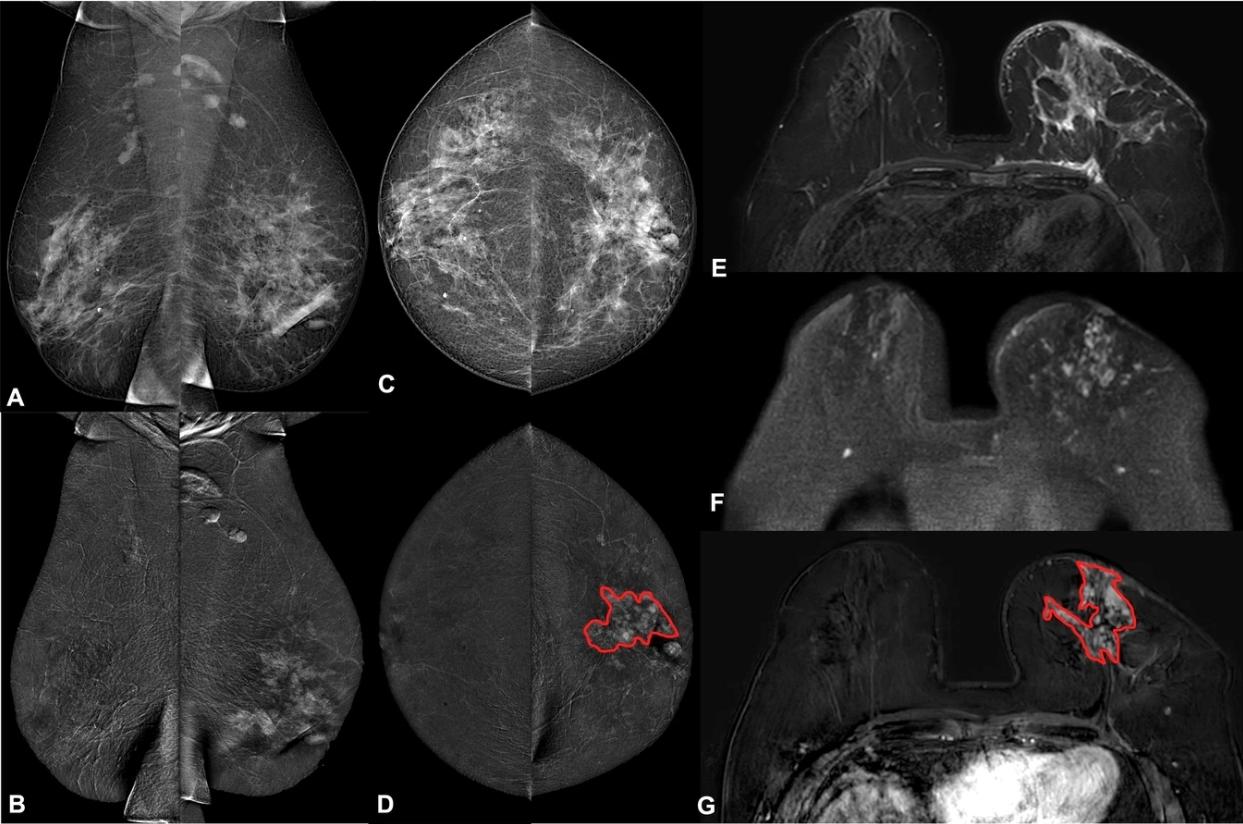

C’est dans le domaine du dépistage mammographique que l’IA a démontré un potentiel particulièrement élevé. Plusieurs études montrent que l’intégration d’algorithmes peut améliorer la précision diagnostique et apporter un soutien significatif dans l’évaluation des risques en vue d’un dépistage personnalisé, tout en réduisant la charge de lecture d’écran des radiologues ou encore en optimisant le tri des examens. « Une revue systématique